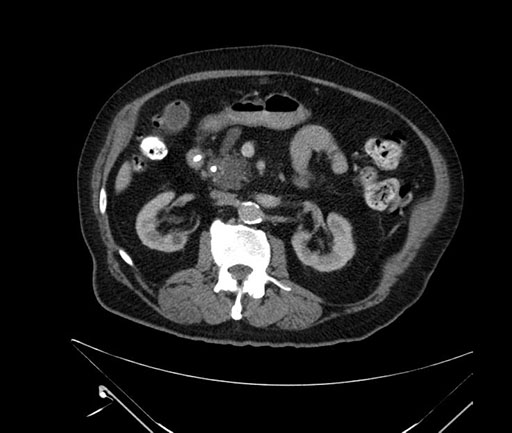

Whipple (pancreaticoduodenectomy) [case 7]

Imaging Analysis

Look through the patient's CT scan to identify any areas of concern for the necessary procedure.

Based on your CT findings, which issue(s) would give reason for "planned slowing down moment(s)" in this case?

Considering a standard Whipple procedure, what step(s) of the operation would you do differently in this case?